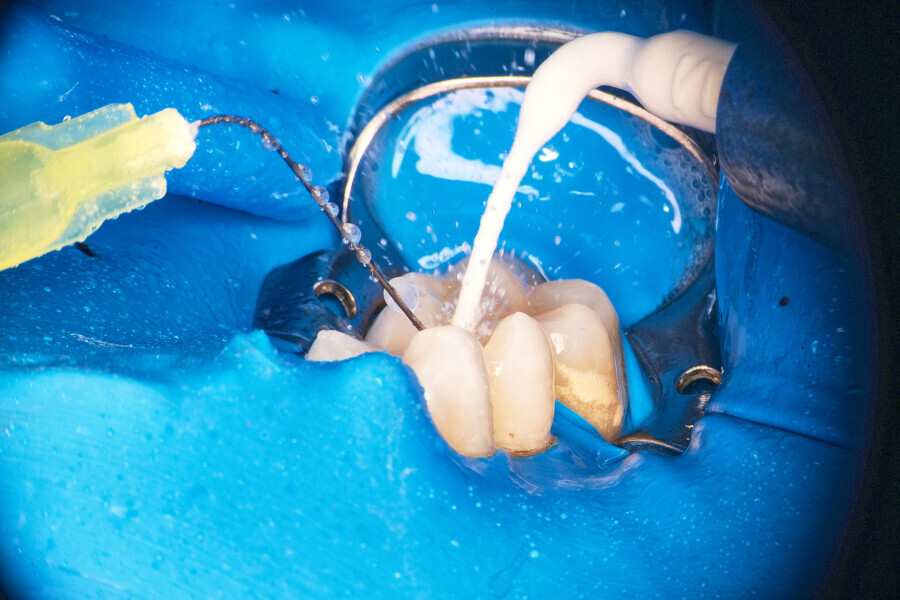

The patient was referred to Dr Witkowski’s dental office for removal of a broken file in the mesial canal and the final endodontic procedure (Fig. 9). Owing to difficulties and the risk of perforation, bypassing of the file was suggested to the patient and she agreed. Proper instrumentation was performed in both the mesial and distal aspects using the R25 RECIPROC blue (VDW; Fig. 10). After this step, extensive irrigation protocol was performed with sonic agitation and continuous irrigation (Fig. 11). The root canal system was then prepared for obturation and obturated using the piston technique (Fig. 12). This technique is capable of obturating even not mechanically instrumented spaces and is very easy to use, especially when there is an obstacle in the canal space such as a broken file (Fig. 13).

Instrumentation was then performed with the R25 RECIPROC blue up to the level of the split, and the split was prepared with the 12.5/0.04 R-PILOT (VDW; Fig. 18). The final irrigation protocol was performed with copious amount of fluids (sodium hypochlorite and citric acid with a final rinse of distilled water; Fig. 19). Obturation was performed with the piston technique, and the restoration was done with composite material (Fig. 20). The patient was referred to the prosthodontist for final restoration. On the final CBCT scan, it was clearly visible that the piston technique had helped to obturate the deep split in the apical area (Fig. 21).

After local anaesthesia, the crown was cut with a high-speed handpiece (Fig. 25). The post was exposed and removed (Fig. 26 & 27). The pulp chamber and root canal orifices were examined for cracks. After inspection, a gingivectomy was performed (Fig. 28) and a dental dam (Kerr Dental) was placed (Fig. 29). The dental dam was sealed with a temporary flowable material (Fig. 30). After sealing the dental dam, the full adhesion protocol with a sixth-generation self-adhesive primer and bonding agent was performed, and the pre-endodontic build-up was created (Fig. 31). Residues of the cement and root canal filling materials were removed with a diamond-coated ultrasonic tip (Woodpecker; Fig. 32). Patency was easily established with hand files (VDW), and the canals were shaped with rotary martensitic files (Poldent) up to 40/0.04. Each step of instrumentation was performed with lubricating cream containing EDTA (VDW; Fig. 33). After each instrument, the canals were flushed with 5.25% sodium hypochlorite (Cerkamed). After reaching the final sizes of the root canals, the irrigation protocol was performed: three sequences of 5.25% sodium hypochlorite and 40.00% citric acid (Cerkamed) activated with an ultrasonic file (MANI), followed by 5.25% sodium hypochlorite activated with the ultrasonic file for approximately 10 minutes (Figs. 34 & 35). The flow of the liquid between both mesial canals was visible.